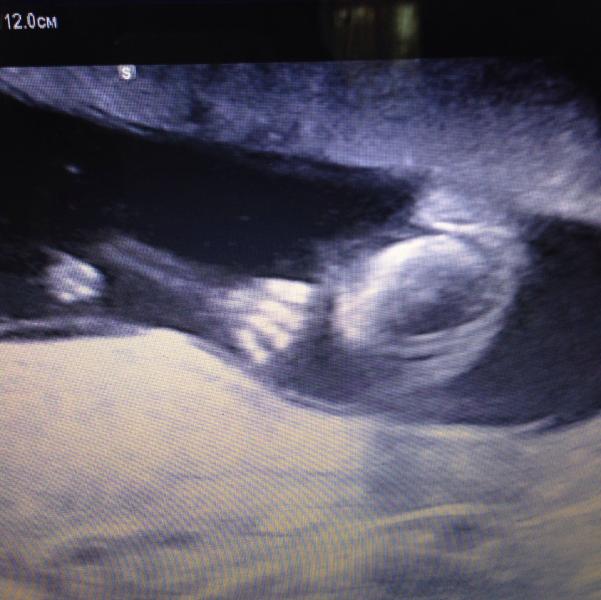

Сходили на платное узи. С ребенком и развитием все хорошо. Меня волновала моя низкая плацентация-но нам этот бред опровергли. Да, и еще, те кто читал мои предыдущие посты-в курсе, что пару дней назад меня тревожили боли в животе. После чего, на приеме в жк сказали, что это кишечник. А сейчас на узи, в платной клинике, мы отчетливо видели, что матка в тонусе((( как вот теперь быть??? Идти к свое гине и показать результат узи? Ну да ладно, главное мы с мужем усидели нашего малыша!!! Вот они, наши...